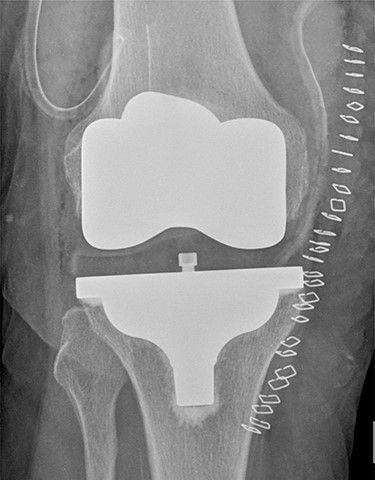

On 17 February 2020, she underwent TKA (Fig. 1). Spinal anesthesia was performed, with the patient in sitting position with one laborious puncture, as referred by the anesthesiologist. The patient received low molecular weight heparin (4000 UI enoxaparin sodium) subcutaneously 12 h after the surgery and a second shot dose 24 h later. On the second post-operative day (19 February 2020), early in the morning, the patient complained of numbness in her lower extremities and low back pain, partially relieved with analgesics. Four hours later, she was complaining for severe difficulty in moving her legs with increased low back pain. The physical examination showed flaccidly paralyzed left lower leg (0/5 left quadriceps, 0/5 left extensor digitorum longus, 0/5 left tibialis anterior and 0/5 left extensor hallucis longus), marked motor function reduction of the right lower leg (1/5 right quadriceps, 2/5 right extensor digitorum longus, 2/5 right tibialis anterior and 2/5 right extensor hallucis longus), sensory loss in both lower limbs, Babinski sign negative bilaterally and preserved sphincter functions. Magnetic resonance imaging (MRI) was required to rule out an acute spinal compression. The images showed a spindle-like mass, mostly intradural, from T11 to L3, hypointense in T2 and heterogeneous in T1 images compressing the dural sac (Fig. 2). Therefore, a diagnosis of acute spinal hematoma was made, and the patient was transferred to the Neurosurgery Department, and surgical decompression was scheduled. A bulky blood clot was removed through a spino-hemilaminectomy of T11 and T12 followed by a posterior dural incision. The source of bleeding was identified in a perimedullary vein on the dorsal surface of the spinal cord that was coagulated. Surgery was performed 3 h after diagnosis, and few hours later, the patient was able to perform a flexion-extension of both lower limbs. She was able to start walking with a walker 24 h later. A low molecular weight heparin (2000 UI Enoxaparin sodium) subcutaneously was started 1 week after surgical decompression. This dosage was increased to 4000 UI 2 days later. On 24 February 2020, a follow-up MRI was performed, and it showed a partial resolution of the hematoma with a confined area of myelopathy at the T12 level (Fig. 3). On the 26 February 2020, the patient started the rehabilitation protocol with the gradual improvement of the neurological status.

Post-operative TKA (Vanguard CR Zimmer Biomet, Warsaw, Indiana).